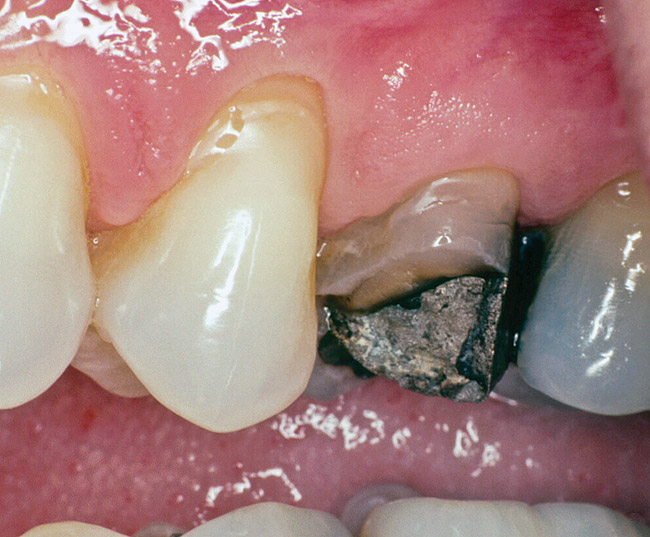

Replacement of existing restorations is responsible for 75% of all operative dentistry.15,19 The reasons for placement and replacement of restorations of direct restorative materials include: primary caries (Figure 1 and Figure 2); recurrent caries (Figure 3); poor margins (Figure 4 and Figure 5); restoration fracture (Figure 6 and Figure 7); tooth fracture (Figure 8); esthetics (Figure 9); non-carious tooth structure lost (attrition, abrasion, abfraction, erosion) (Figure 10); and pain/sensitivity.

Fig. 6 Restoration fracture. Fractured isthmus of an amalgam restoration.

Figure 6  Restoration fracture. Fractured isthmus of an amalgam restoration.

Figure 6